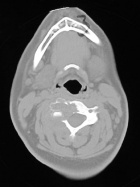

C.F. - 15 year old female presents with a six month hx of neck pain.

Zoom image: Radiological image Radiological image.